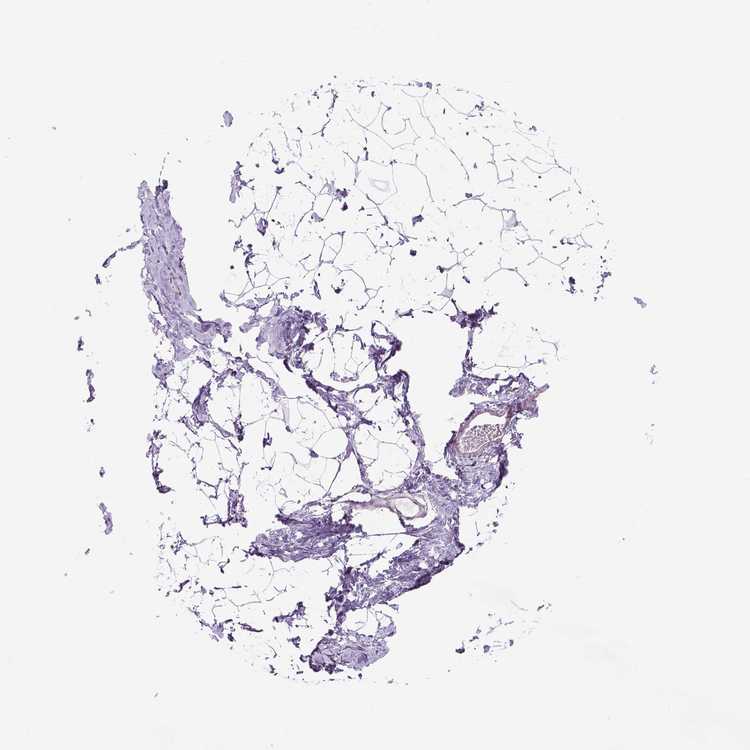

BREAST - Antibody stainingi

Antibody staining in the annotated cell types in the current human tissue is reported as not detected, low, medium, or high, based on conventional immunohistochemistry profiling in selected tissues. This score is based on the combination of the staining intensity and fraction of stained cells.

Each image is clickable and will lead to virtual microscopy that enables deeper exploration of all samples and also displays staining intensity scores, fraction scores and subcellular localization as well as patient and tissue information for each sample.

Antibody HPA012636

Adipocytes Not detected

Glandular cells Low

Myoepithelial cells Not detected